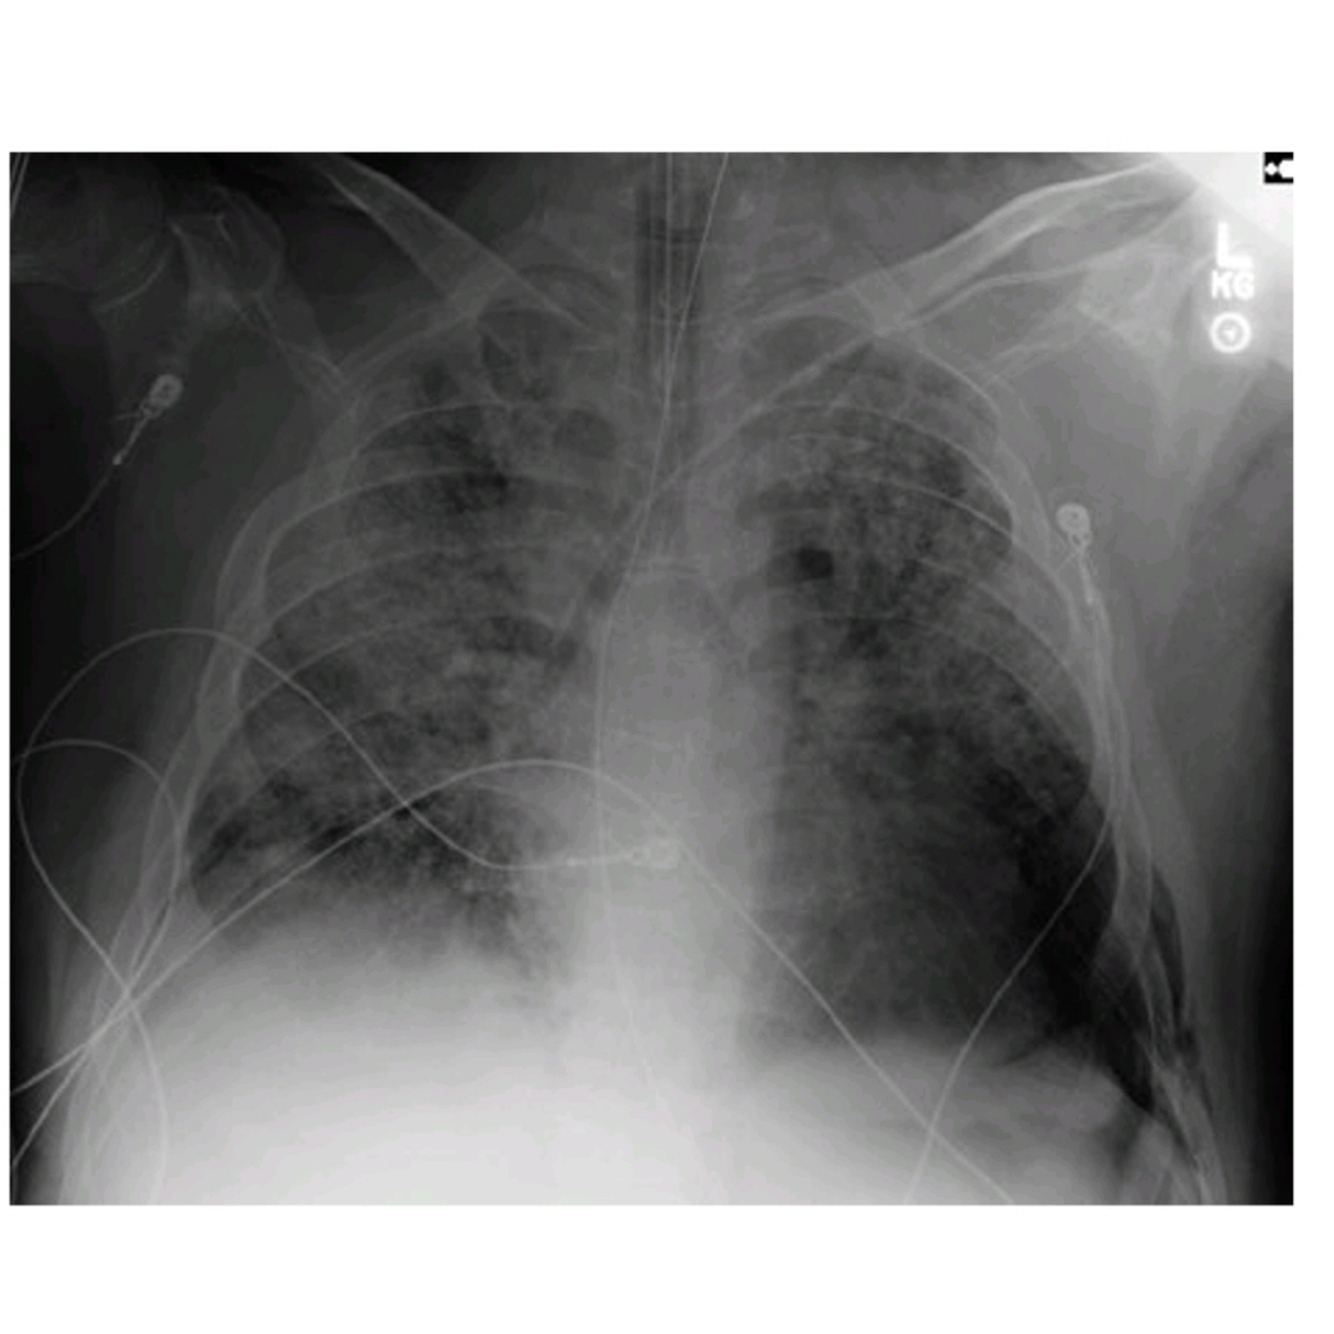

What do the images above show and what is the differential diagnosis based on the appearance seen in the images above?

○ The chest X-ray (Fig. 47.1) shows diffuse bilateral coalescent opacities, whereas the CT chest (Fig. 47.2) shows ground-glass opacification, reflecting an overall reduction in the air content of the affected lung. It is also possible to visualize bronchial dilatation within areas of ground-glass opacification.

Differential diagnosis include

(a) ARDS,

(b) congestive heart failure,

(c) pulmonary hemorrhage,

(d) pneumonia,(

e) transfusion-related acute lung injury, and

(f) non-cardiogenic pulmonary edema.